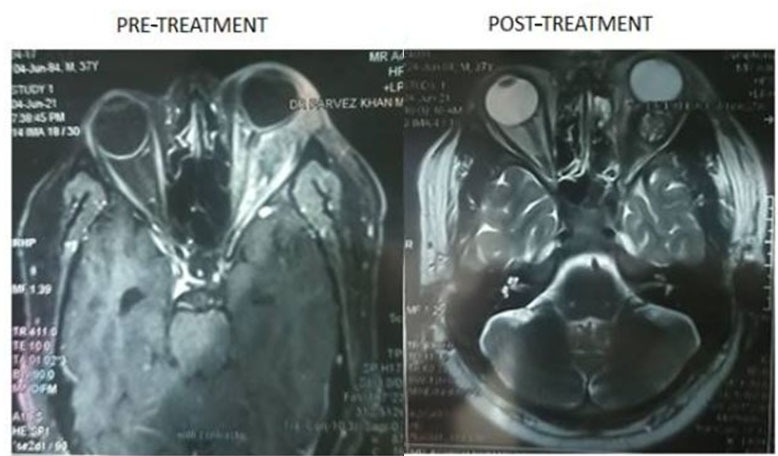

Contrast-enhanced magnetic resonance imaging (CEMRI) of orbit and peripheral nervous system (PNS) revealed heterogeneous altered signal intensity lesion seen in left orbit involving superior, inferior and lateral rectus muscles as well as left optic nerve and causing proptosis of the left eye globe and involvement of frontal, maxillary, ethmoid and sphenoid sinuses. No obvious abnormalities were seen on CEMRI brain (Figure 2).

Figure 2: Pre-treatment—T1-weighted axial MRI shows left isointense signal intensity lesion, involving intraconal and extraconal spaces, extending along orbital apex. Post-treatment— T1-weighted axial CEMRI shows decrease in hyperintensity of the extraocular muscles and proptosis of left eye after treatment of mucormycosis.

Contrast-enhanced magnetic resonance imaging of brain, PNS, and orbit also showed improvement after the treatment of the patient which can be assessed by decrease in the hyperintensity of the extraocular muscles involved and resolvement of the proptosis and sinusitis (Figure 2).